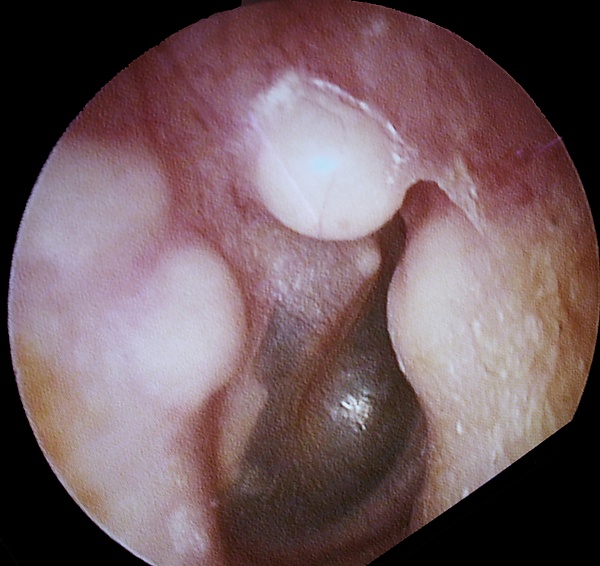

Диагностика

Диагноз остеомы ставят на основании клинико-рентгенологических данных. Дифференциальный диагноз между хроническим остеомиелитом и остеогенной саркомой легко установить на основании рентгенологической картины и течения заболевания.